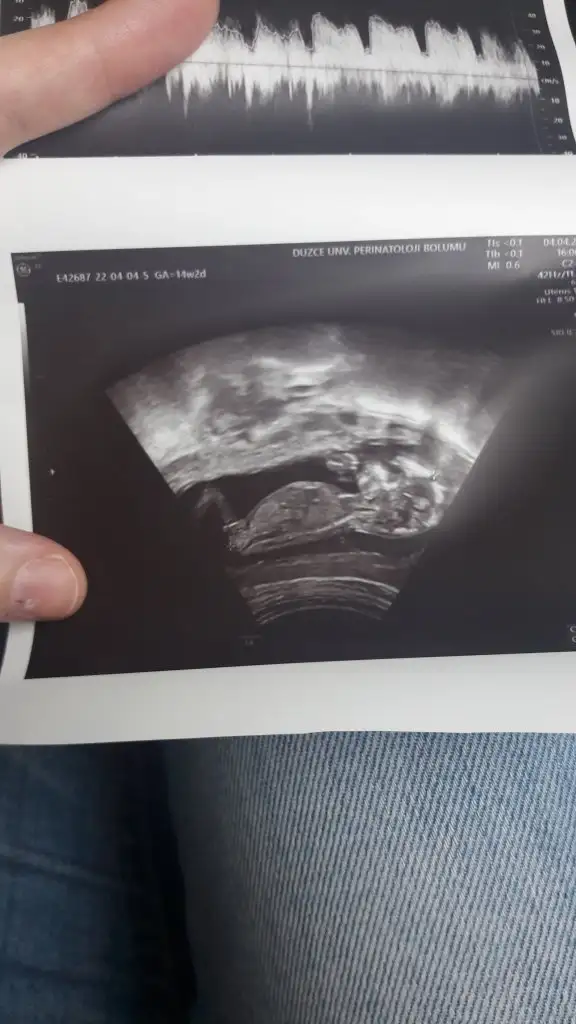

Nur ablacım doktor net söylemek için biraz daha beklemeyi tercih etti bende ısrar etmedim 1 ay sonraya kaldı😢, bu da 13+6 karından. Hala tahminin aynı mı sence merak ettim?